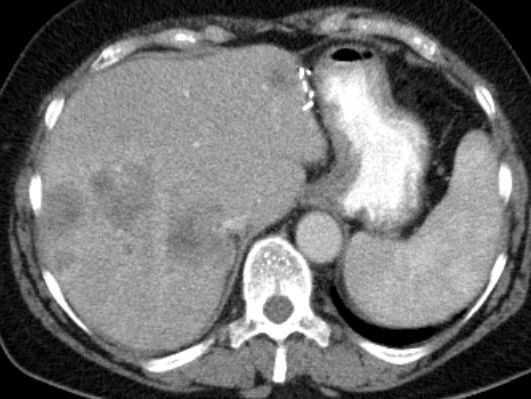

| Leber - Metastasen | 70-jähriger Mann, der vor 1 Jahr ein primär hepatisch metastasiertes Sigmakarzinom hatte. Sigmaresektion, R2. Dann Panitumumab/FOLFIRI). Lebersegmentresektion II , III , VIII , VII. Thermoablation VIII. Erneut ausgedehnte Lebermetastasen. | ||

![]() |

![]() | ||